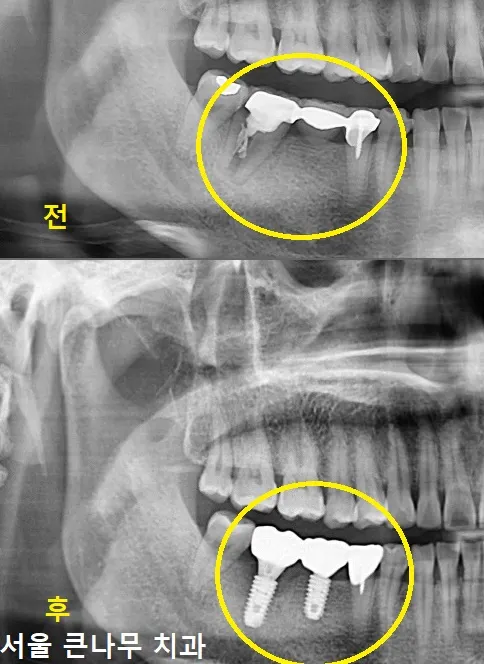

환자분께서는 4개 치아로 이어져있던 브릿지 중 왼쪽 뿌리 끝에 염증이 발견되었습니다. 이로 인해 브릿지 제거 후 비어있는 공간에 임플란트 를 하나 식립하였습니다. 또한, 뿌리 끝 염증이 있는 2개 치아는 재신경치료 후 지르코니아 크라운 으로 다시 수복해주었습니다.

1년이 지난 지금은 뿌리끝 염증이 많이 사라진 상태입니다.